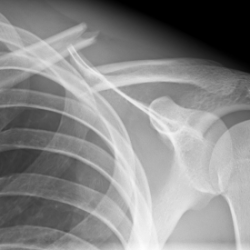

Röntgenbilder